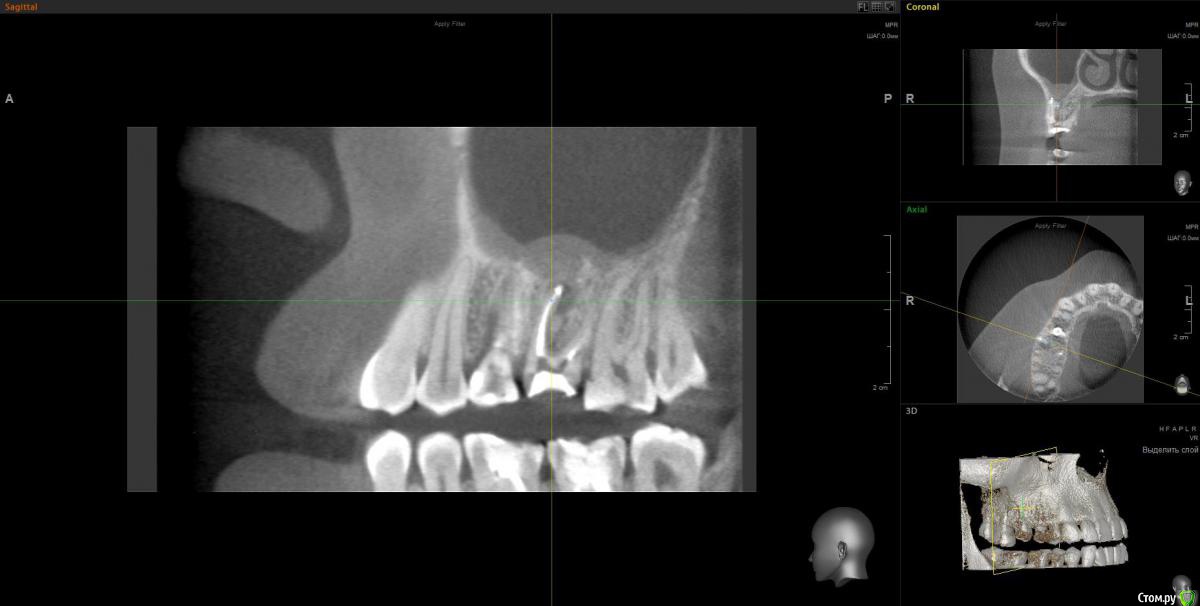

Весна2009 Опубликовано 30 января, 2017 Автор Поделиться Опубликовано 30 января, 2017 Снимок Ссылка на комментарий

Весна2009 Опубликовано 30 января, 2017 Автор Поделиться Опубликовано 30 января, 2017 В день установки импланта Ссылка на комментарий

Весна2009 Опубликовано 30 января, 2017 Автор Поделиться Опубликовано 30 января, 2017 Размер пришлось уменьшить,н е загружалось, качество стало хуже Ссылка на комментарий

anvladd Опубликовано 31 января, 2017 Поделиться Опубликовано 31 января, 2017 (изменено) Как с носом, не гайморит ли ? 3 d бы глянуть, хотя бы этот сегмент. Изменено 31 января, 2017 пользователем anvladd Ссылка на комментарий

Весна2009 Опубликовано 31 января, 2017 Автор Поделиться Опубликовано 31 января, 2017 Вы тоже думаете, что имплант в гайморовой? Ссылка на комментарий

wladdX Опубликовано 2 февраля, 2017 Поделиться Опубликовано 2 февраля, 2017 Несколько скриншотов на скорую руку. Ссылка на комментарий